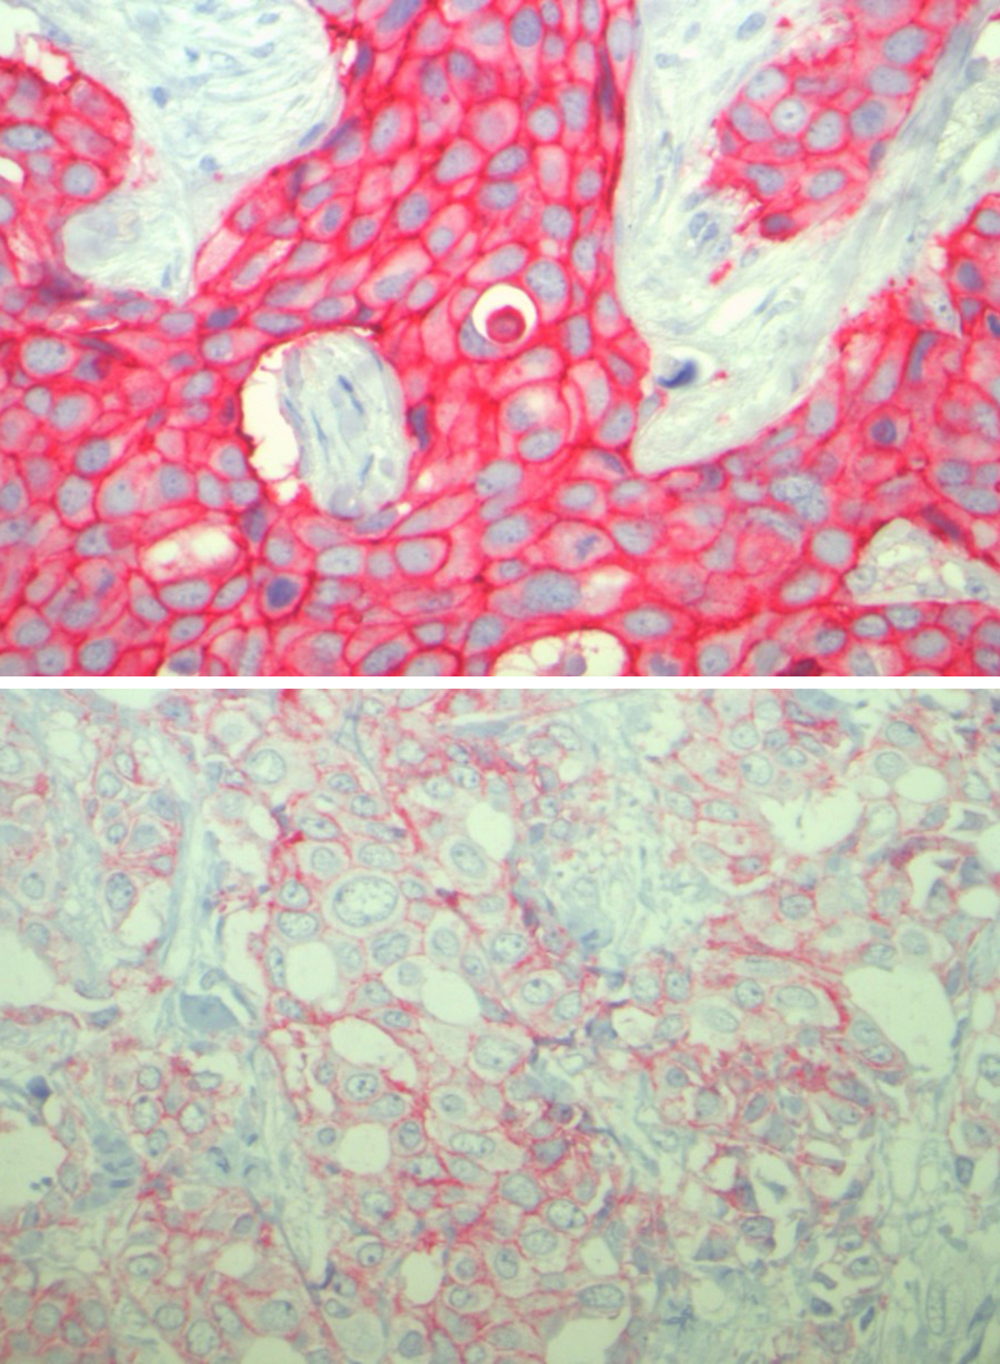

Bislang galt eine zielgerichtete Therapie nur dann als erfolgversprechend, wenn der Tumor eine sehr stark erhöhte Konzentration von HER2 aufweist. Das Forschungsteam um Denkert und Loibl untersuchte Brustkrebsgewebe von 2310 Patientinnen, die eine Kombinationschemotherapie erhalten hatten.

„48 Prozent dieser Gewebeproben zeigen eine schwach-positive Konzentration von HER2“, berichtet Denkert. „Wie wir herausfanden, lässt sich Tumorgewebe mit schwacher Positivität für das HER2-Protein als eigener Brustkrebs-Subtyp charakterisieren, der sich von Tumoren unterscheidet, die gar kein HER2-Protein aufweisen.“ Das wirkt sich insbesondere auf das Überleben der Betroffenen aus: „Wenn im Tumor das HER2-Protein in geringer Konzentration vorliegt, ist die Überlebenswahrscheinlichkeit der Betroffenen größer, als wenn das Gewebe gar kein HER2 enthält“, legt Loibl dar.